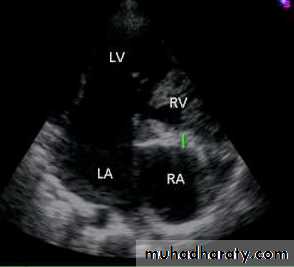

Tricuspid atresia accounts for approximately 2% of all congenitalheart defects . The absence of the tricuspidvalve results in a hypoplastic right ventricle. All systemic venous return must cross the atrial septum Into the left atrium. A PDA or VSD is

necessary for pulmonary blood flow andsurvival.

Diagnosis

ECG shows LVH and Lt axis deviation.

CXR shows cardiomegaly with decreased pulmonary blood flow

Echo is diagnostic and shows the abnormalities.